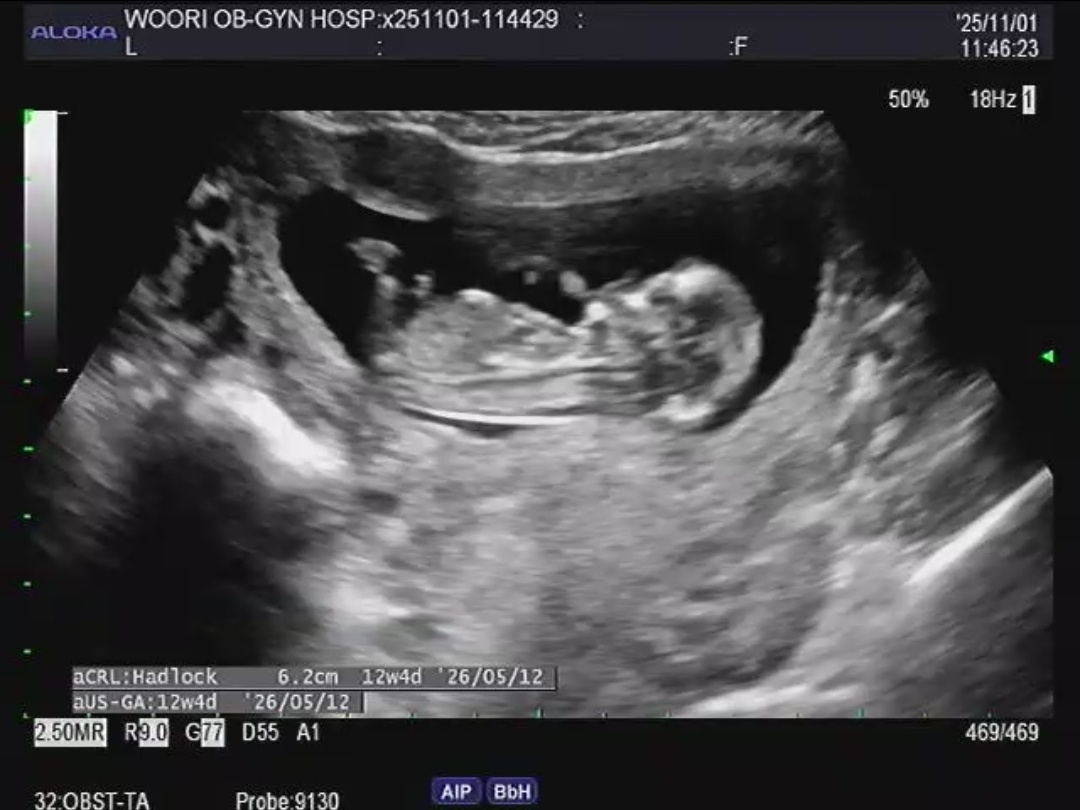

12주4일 아기성별 투표 부탁드려요~♡

딸일까요 아들일까요?!